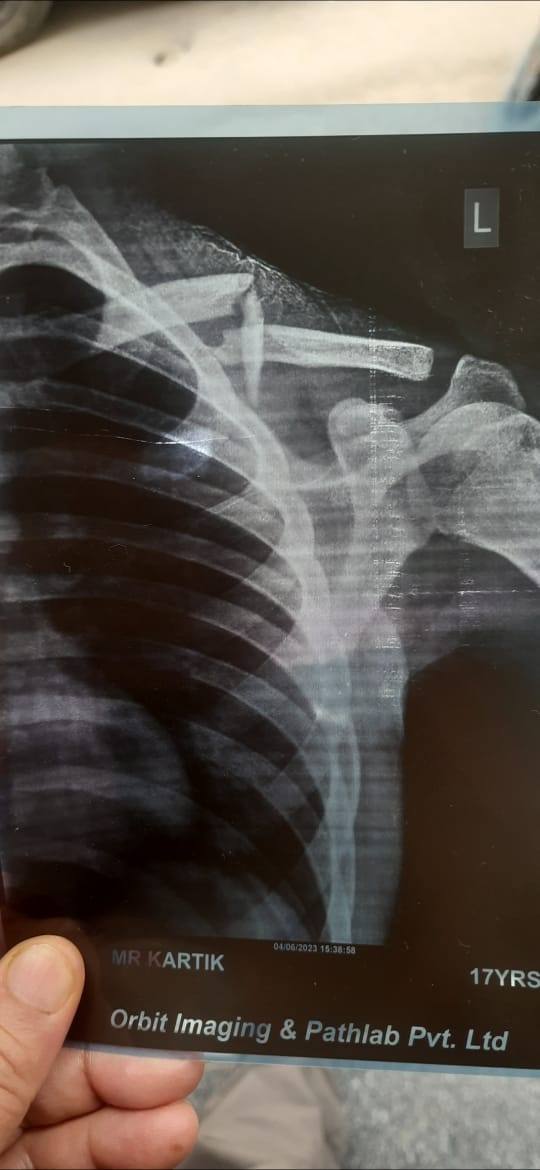

My colarbone facture

Sir my clore bone broken please give me suggestion sir bina survery ka thik hujgyi